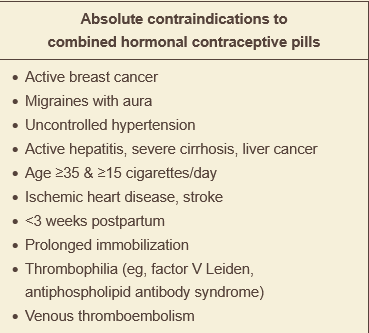

what are the absolute contraindications to ocps?